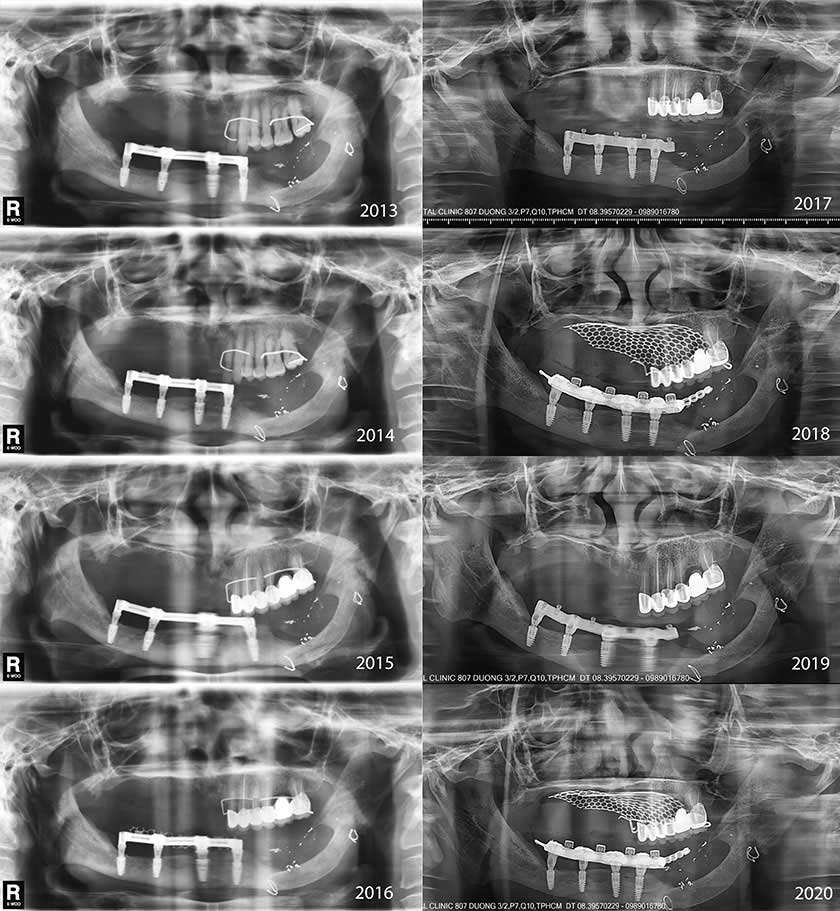

An overdenture supported on a bar-retained, implant-supported system was delivered 6 months later (Fig 3). The prosthesis was designed with distal cantilevers, especially on the left side where the fixed prosthesis was opposed. The position of the posterior abutments on the denture was located between the premolar and molar on the right and on the mesial of the second premolar on the left (Fig 3). The left cantilever extended to 2 teeth composing the 2 molars, and the right cantilever extended to 1 tooth. On the left, the denture was adjusted so that only the mesial part of the left second molar occluded to the opposing tooth. The patient was scheduled for continuous follow-up assessments. After 3 years, the bar-retained supporting system appeared loose and was replaced with the new CAD/CAM milled bar with the OT Equator system on the same 4 implants (Fig 3). The total follow-up time was 82 months (Fig 4).

Figure 4. Orthopantomographic images of annual follow-ups from 2013 to 2020 present peri-implant health with good osseointegration.

After 7 years, all 4 dental implants remained stable and functioned well without any problems. The IBG maintained good quality based on orthopantomography. The peri-implant and soft tissues were healthy. The patient was satisfied with the esthetic and functional outcomes of the prosthesis. No nerve dysfunction was reported.

The overdenture was designed to maintain long-term esthetic and functional use. For the overdenture on 4 implants, the amount of distal cantilever is closely related to the anterior-posterior (A-P) spread of the denture.33 Superimposing the locations of the 4 abutments on the occlusal surface of the denture helped to locate the landmarks that were used to value the relation of cantilever length (yellow line) and the A-P spread (blue line) (Fig 3E). The line of posterior-most cantilever (the distal most of the second molars) was the x line. According to Carl Misch,33 the cantilever length to the x line (Fig 3E) was 1.5 times the A-P spread. In this case, only the mesial half of the left second molar contacted the opposing tooth, which reduced the loading stress; therefore, the cantilever length measured from the occlusal contact points of both sides (y line) was just 1.25 times the A-P spread. This length is suitable to the Misch recommendation for cantilever. As a result, all 4 implants maintained good osseous integration and minimized bone loss during the 7-year follow-up, presenting orthopantomographic evidence.